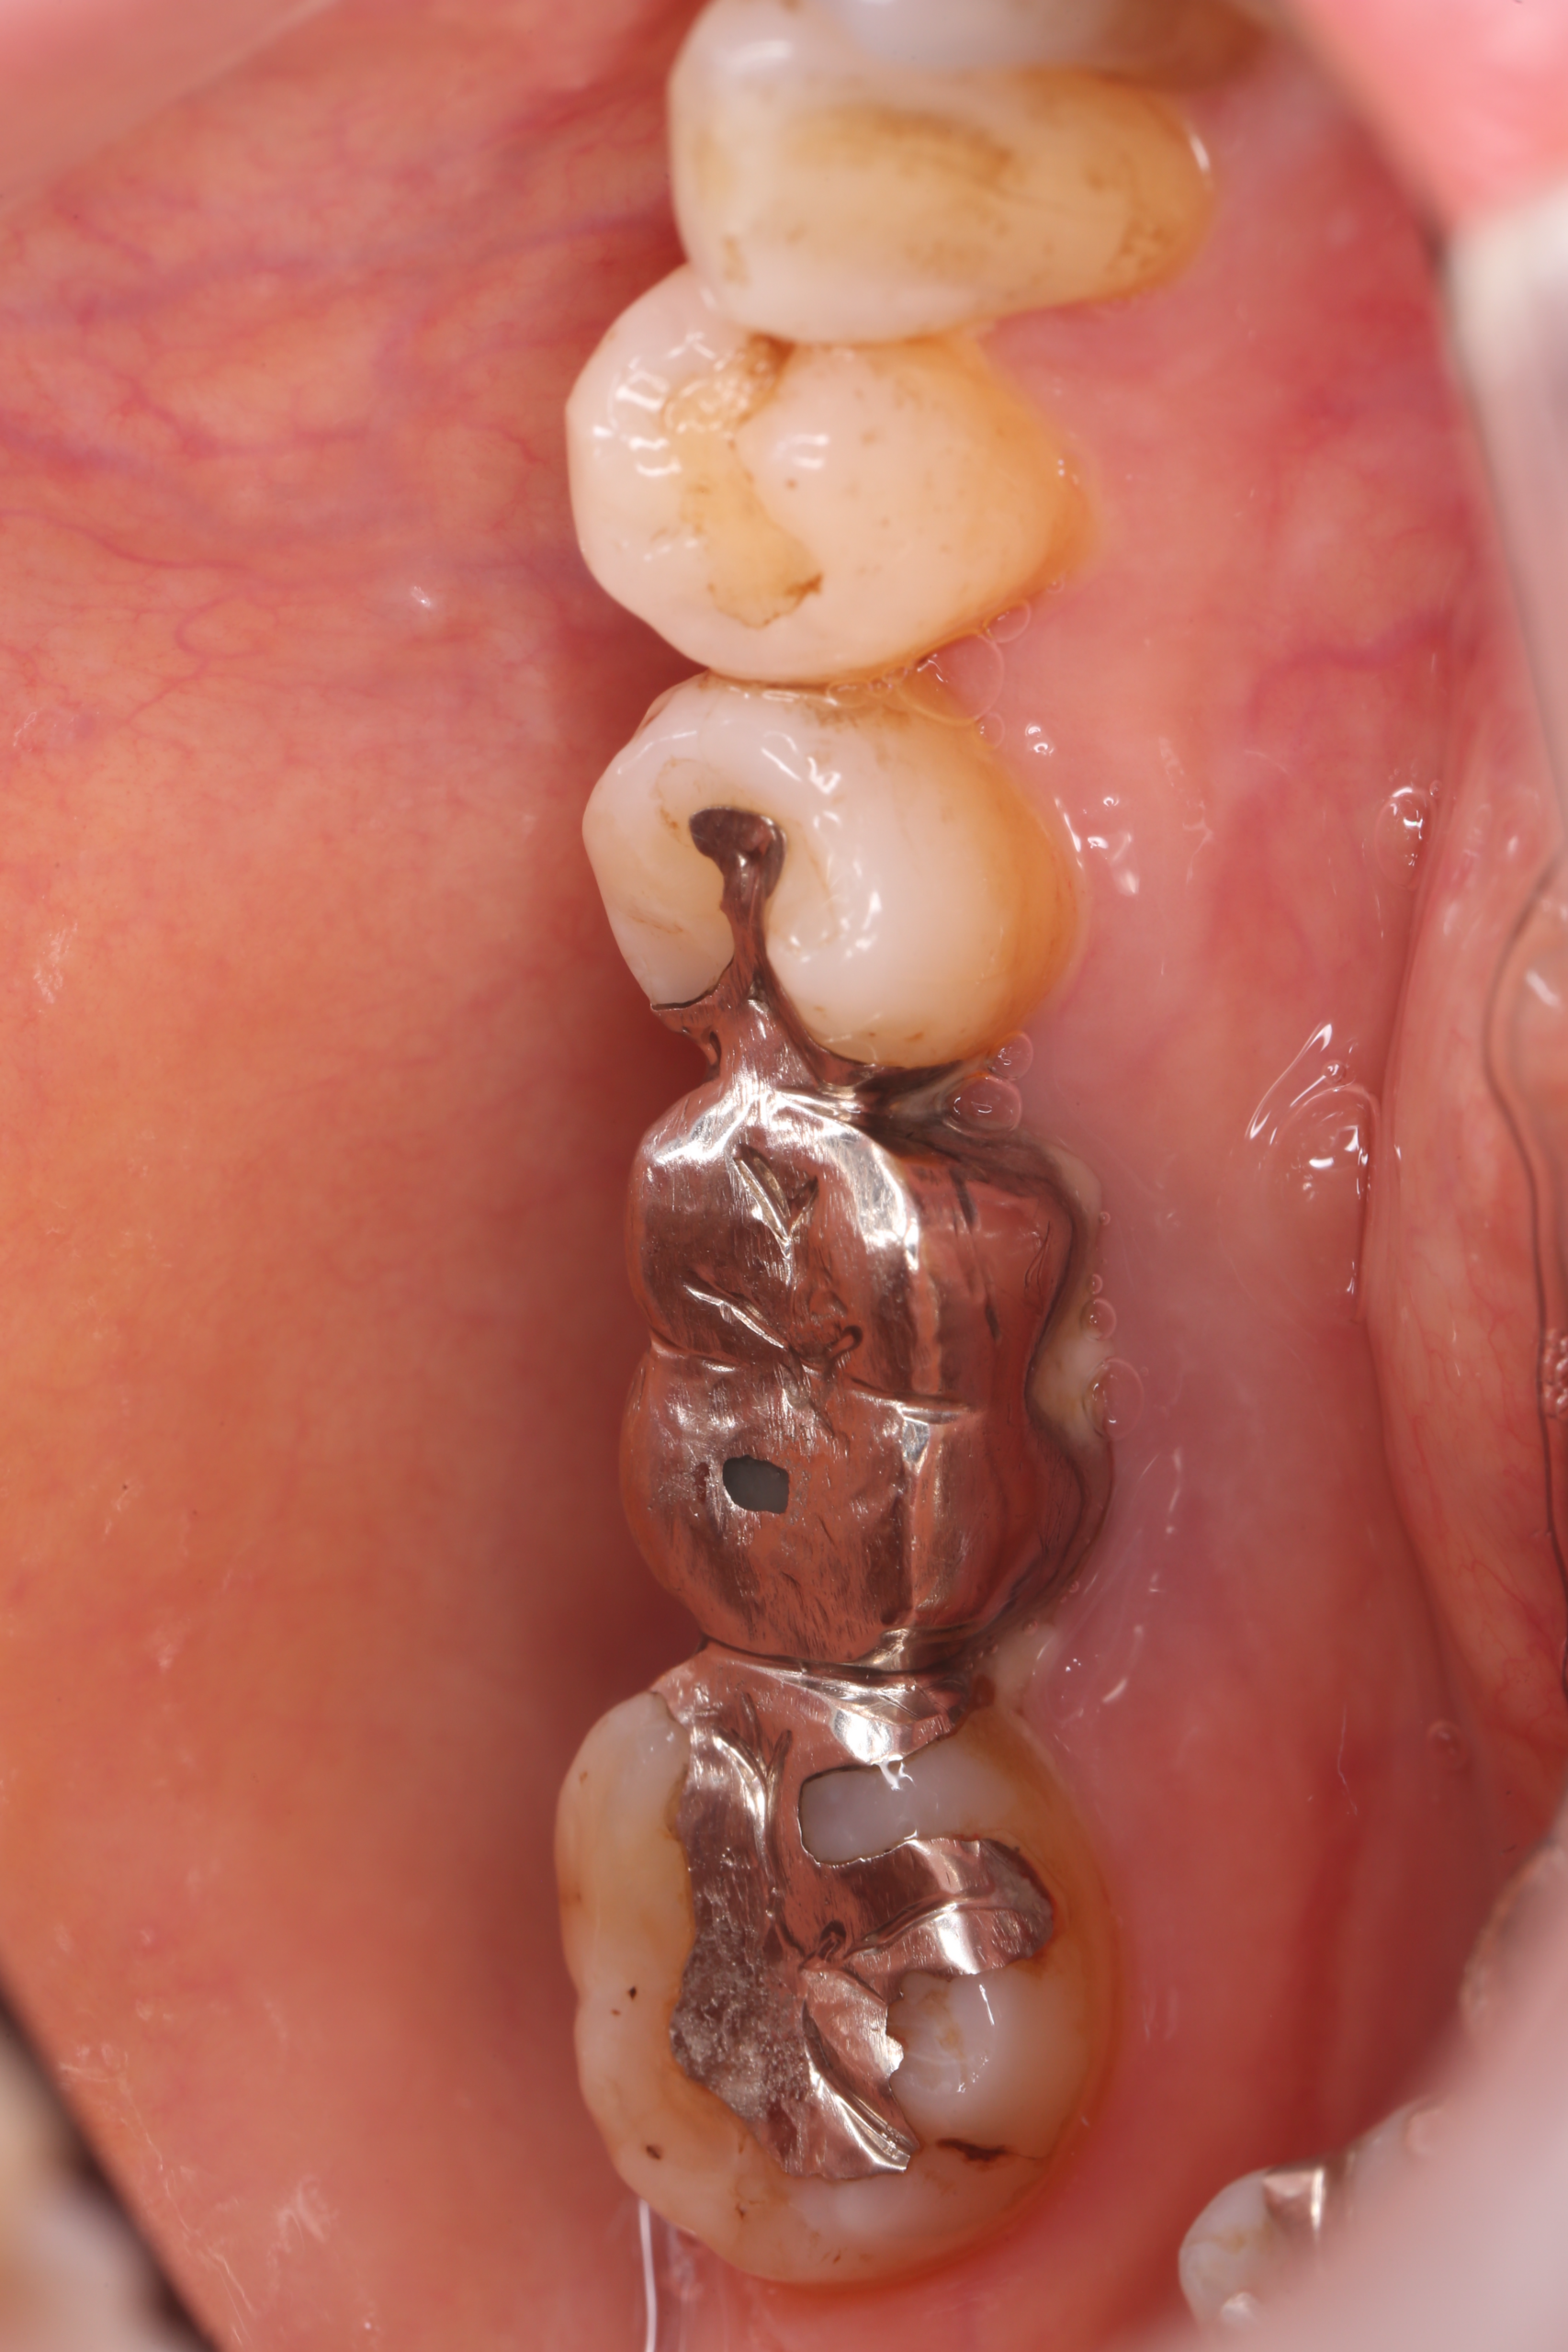

術前の状態です。奥歯の一番後ろの歯にメタルのインレー、後ろから二番目にメタルのクラウン、三番目にメタルのインレーが入っています。

後ろから一番目の歯はe-max pressのインレー

後ろから二番目の歯はインプラント治療(ジルコニアクラウンをスクリューリテインとしました)

後ろから三番目の歯はe-max pressのインレー

で治療を行うことを患者さんと相談し、決定しました。